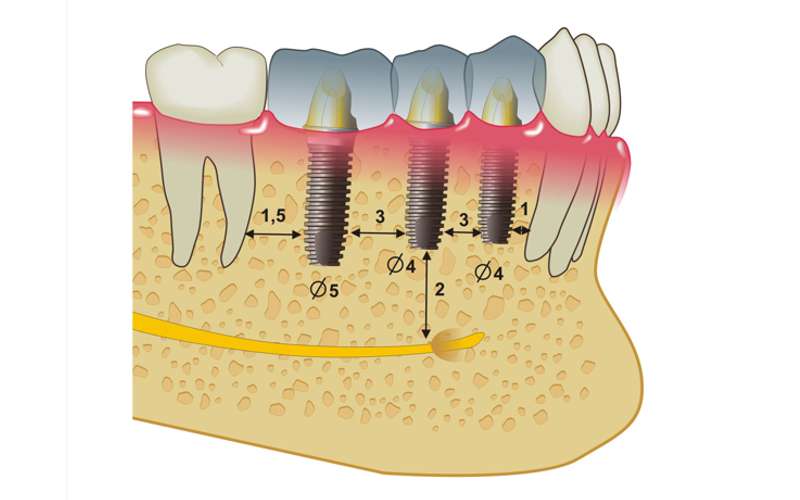

- Implantes Dentales